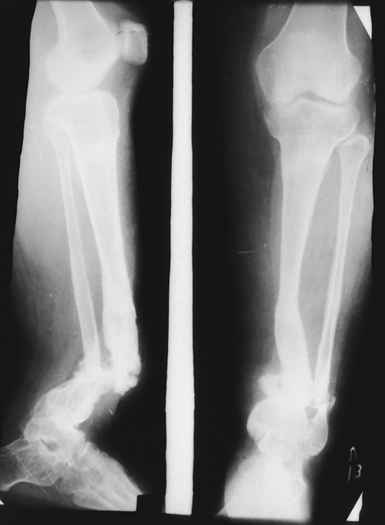

Женщина 28 лет, пошедшая 13 предыдущих оперативных вмешательств по-поводу ВПБ имела 9 см. укорочения.

На первом этапе аппаратом Илизарова закрыто устранена деформация голени.